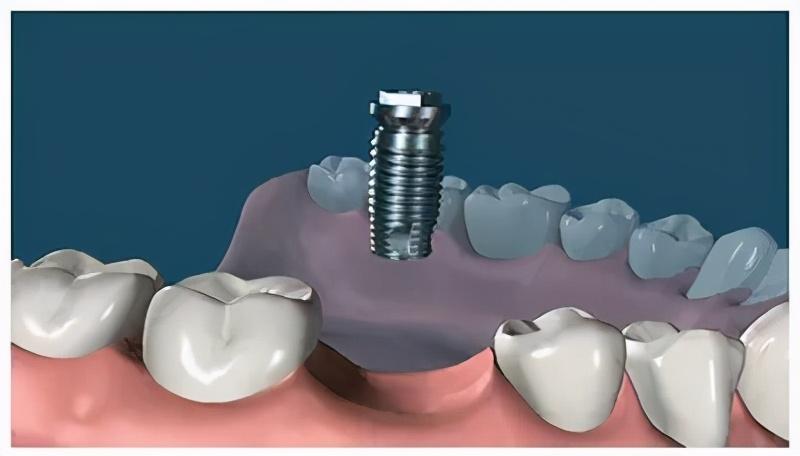

種植牙,全稱為人工種植牙,分成三個(gè)部分:種植體(人工牙根)、基臺(tái)(連接體)和牙冠(牙齒)。

種植體是一種高度精密的螺絲構(gòu)造,它外部的螺紋和微表面結(jié)構(gòu)與牙床骨接觸,引導(dǎo)牙床骨細(xì)胞生長(zhǎng)到種植體表面,以達(dá)到種植體與牙床骨充分結(jié)合,增強(qiáng)其咀嚼力量及穩(wěn)定性能的目的。

確定能手術(shù)后,才會(huì)診斷取模、制定種植牙方案。(第一次大約1個(gè)多小時(shí))然后正式開始種植牙手術(shù)。在牙槽骨上制備一個(gè)孔,植入人工種植體。將牙骨床內(nèi)嚴(yán)密縫合,大約一個(gè)星期后可以拆線(這次大概7--10天)。

注明:此植體只是模擬位置,不做確切種植位置。